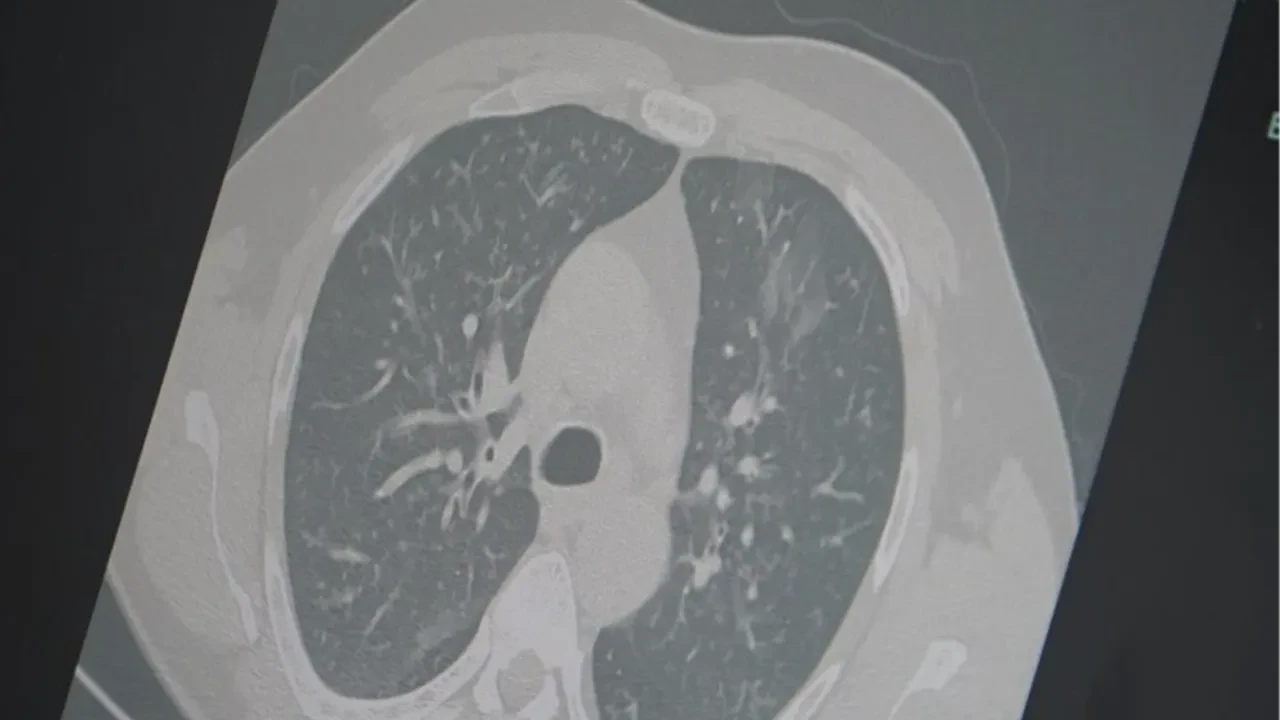

Son dönemdeki hava şartlarının belirsizliği yurt genelinde hastalıklara davetiye çıkarmaya devam ediyor. Ülke genelindeki solunum yolu enfeksiyon vakalarında artış yaşanmasının ardından uzmanlardan 3'lü salgın uyarısı geldi. Göğüs Hastalıkları Uzmanı Prof. Dr. Şevket Özkaya, aynı anda görülen influenza (grip), kovid-19 ve RSV virüslerinin toplumda "3’lü salgın" etkisi oluşturduğunu belirterek vatandaşları dikkatli olmaları konusunda tedbirli olmaya davet etti.